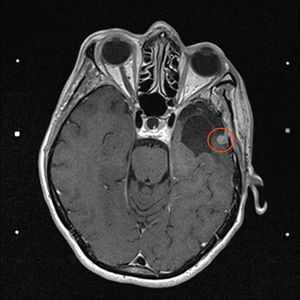

12. November 2021: Innerhalb der Messungenauigkeit

Heute war ich mit Stephan in der Ambulanz der Neurochirurgie zur Auswertung des MRTs, dass vor 10 Tagen erstellt wurde. Das Ergebnis ist erfreulich:

• der Tumor ist sehr klein (< 10mm) und deshalb stört er  nicht

• der Tumor ist, wenn überhaupt, sehr wenig gewachsen und so genau misst das Gerät nun auch nicht (vielleicht habe ich nicht still gelegen?!)

• durch die Gamma-Knife-Bestrahlung kann man das Wachstum des Tumors beschränken, die Strahlen entfernen ihn nicht

• falls doch mal Wachstum auftreten sollte, sitzt das Ding an einer guten Stelle und aus Sicht des Neurochirugen ist es "im Notfall" nur eine kleine Sache ihn zu entfernen

Also alles prima, alle Aufregung unnötig. Ich lebe nun halt mit einem Tumor im Kopf weiter und lassen ihn in 6 Monaten neu inspizieren. Ich bin erleichtert, es geht mir prima und auch die Schulternschmerzen haben sich verzogen. Gestern konnte ich auch schon wieder 15km langsam joggen.

2. November 2021: Leider etwas gewachsen

Heute war ich im MRT im Bremen. Der Befund des auswertenden Arztes ist, dass er der Meinung ist, dass der Tumor etwas gewachsen ist. Ich habe mir die Bilder angesehen und versucht diese Aussage zu verstehen. Vermutlich ist sie richtig, aber das Wachstum ist nicht heftig nur vielleicht von 0,7 cm auf 0,8 cm. Aber Gamma-Knife hat es offensichtlich nicht entfernt.